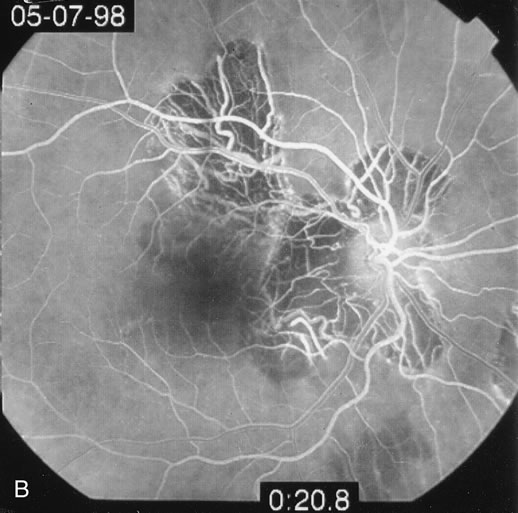

The classic findings in the acute cases are lesions of variable size that are hypofluorescent in the early phase of the fluorescein angiogram. In the late phases of the angiogram there is hyperfluorescence of the lesions. In the late phases, there also may be leakage from the disc as well, and there also may be staining of the retinal vessels because of the vasculitis. With resolution of the disease, there still may be a mottled pattern of fluorescence correlating with the areas of pigment clumping and pigment atrophy (Fig. 8).

Fig. 8. A. Early fundus angiogram showing hypofluorescence of the acute posterior multifocal placoid pigment epitheliopathy (APMPPE) lesions. B. Later stage of the angiogram showing staining of the APMPPE lesions.